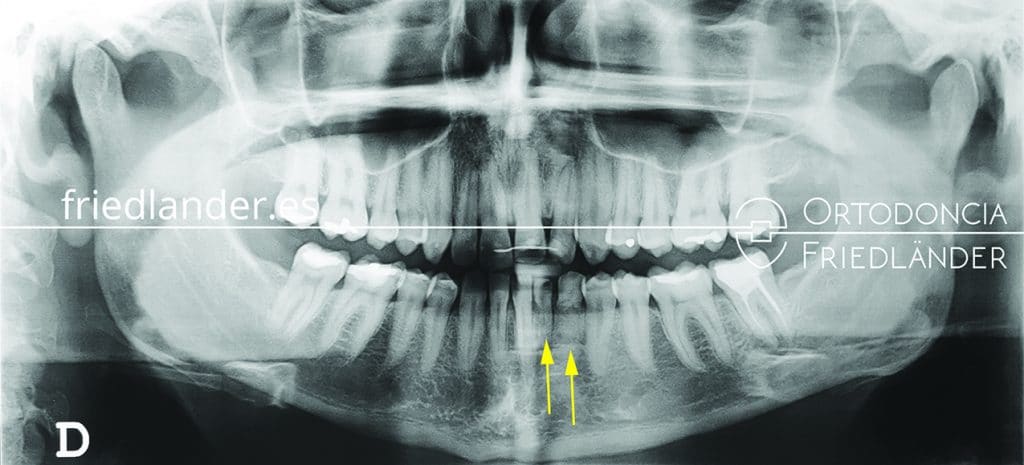

En este caso los dientes ausentes son dos incisivos inferiores del lado izquierdo y el canino inferior izquierdo. Estas agenesias son bastante raras ya que las más frecuentes son de las muelas de juicio, incisivos laterales superiores y segundos premolares inferiores (los casos 16 y 17 son dos tratamientos de agenesias de segundos premolares inferiores solucionados de dos maneras diferentes). En la primera visita, la paciente nos comenta y le preocupa que algún diente de leche, todavía presente en boca, tiene movilidad, tiene miedo de perderlo y quedarse con un hueco entre los dientes. Normalmente la presencia de un diente de leche en la edad adulta nos puede indicar que el diente definitivo que le sigue está ausente. Mediante una radiografía panorámica (una ortopantomografía) se diagnostica rapidamente las agenesias que tiene la paciente.